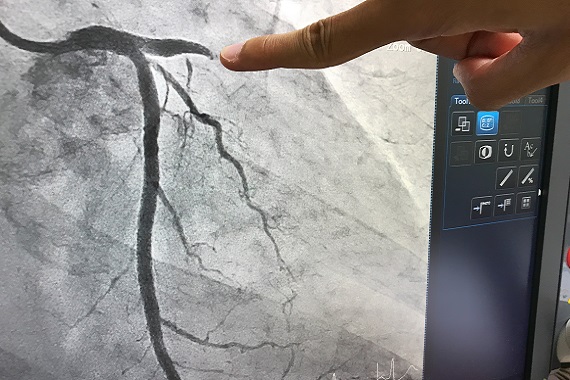

From 2011 to 2014, the research team screened 850 people experiencing a STEMI heart attack. Their doctors performed an angiogram, an X-ray procedure that allows doctors to visualise the coronary arteries to identify blocked or narrowed areas. 296 patients were found to have partial blockages in one or more of the vessels supplying their heart, in addition to the ‘culprit’ blockage that directly caused their heart attack. Participants in the trial either: